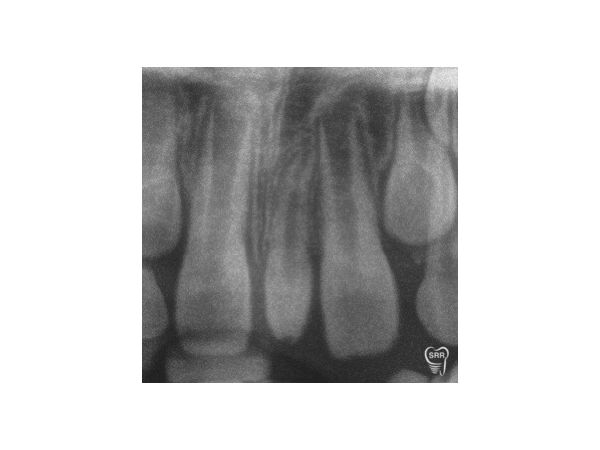

Сверхкомплектный 21-й зуб бочкообразной формы располагался между резцами верхней челюсти, имел два бугра. Реакция на холод и простукивание безболезненная.

K00.10 Сверхкомплектный 21-й зуб в области резцов (мезиодентия).